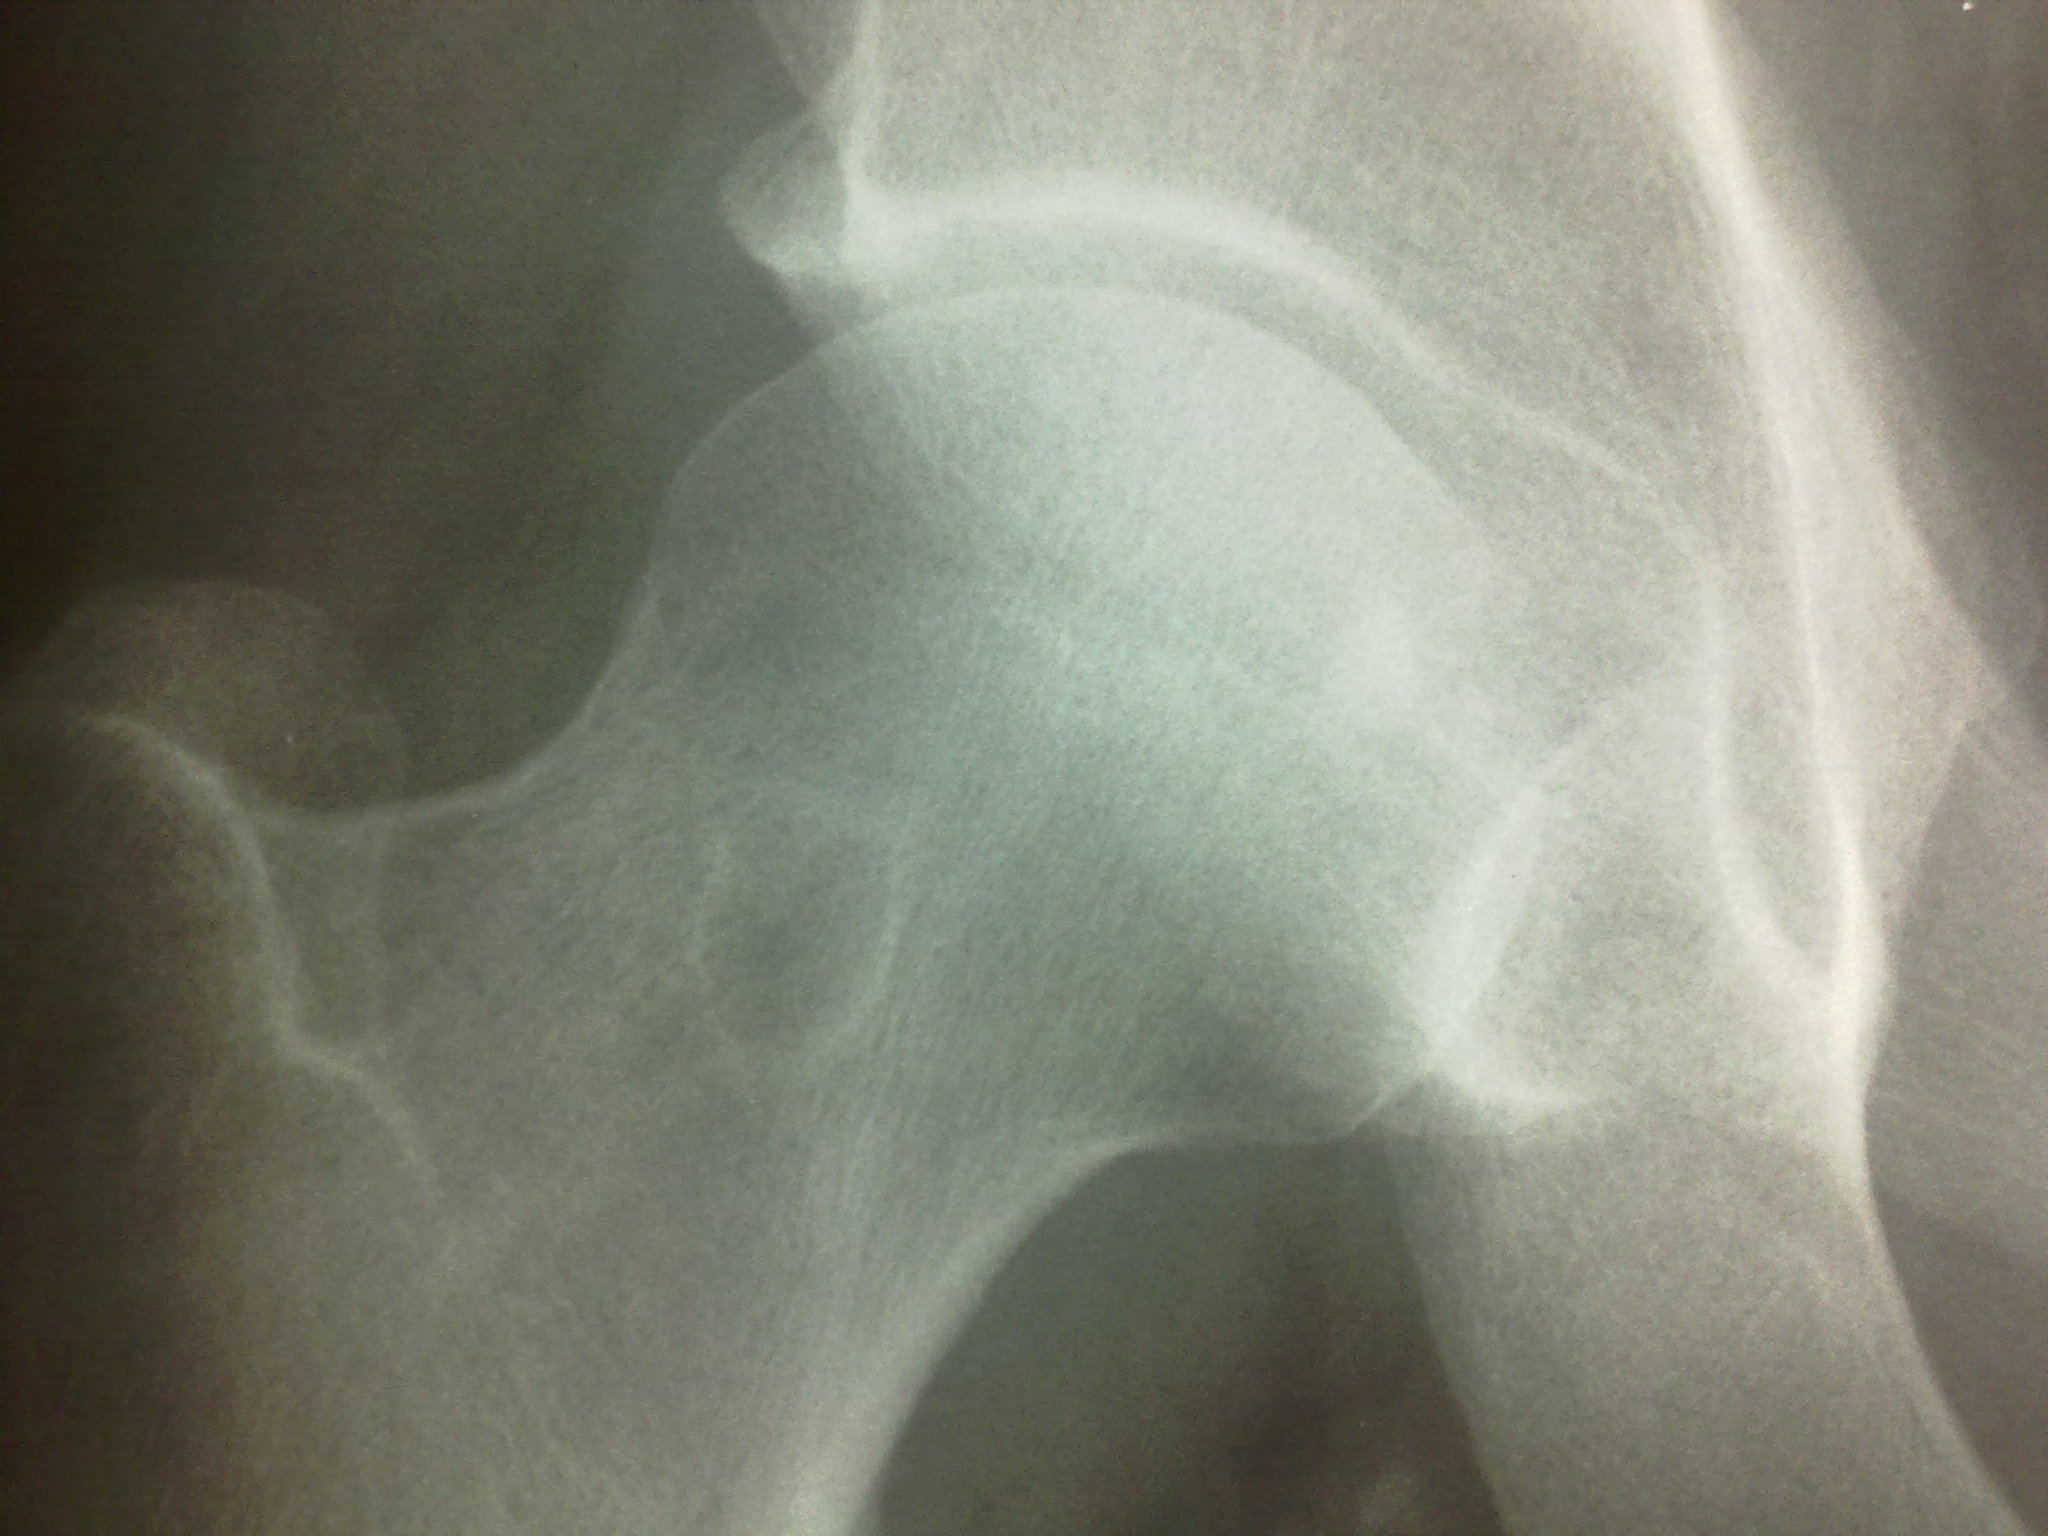

Мужчина пришел на МР-исследование правого тазобедренного сустава.Рентгенограммы также принес( удивительно- скорее,исключение,чем норма). Пока выставляю рентенограммы завтра МР-картинки.

У мужчины уже лет 5 назад были выявлены склеротические очаги в подвздошной и бедренных костях, тогда же подозревали бластические метастазы, но обследования показали норму ( судя по записям в амбулаторной карте).

А вот про очаг в шейке данных не было.

А снимки 5-летней давности есть? интересно было бы динамику посмотреть.

Я бы сказала: в крыле - остеома (то же - эностоз, компактный островок, но при таких размерах, как-то странно островком называть), вот в головке - компактный островок. В шейке - четкий узкий ободок склероза указывает на доброкачественный характер, вероятно - дегенеративная киста; интраоссальная липома обычно в межвертельной области. Кальцификация стенок сосудов.

Спикулы не усматриваете, уважаемые дамы?

Видите ли, Петрович истинные спикулы перпендикулярны плоскости кортикального слоя.

Ну, пусть не истинные..., какие-то неравновеликие лучи, направленные радиально от большого остеосклеротического фокуса. Мне кажется, это признак роста.

Всеже отсутствие динамики за 5 лет - в пользу доброкачественного процесса. Мts или остеосаркома представляются очень сомнительными... На мой взгляд, спикулообразность контуров в данном случае обусловлена либо груботрабекулярной перестройкой структуры, либо сформирована суммационно.

В тазу и в бедренной кости совсем разные вещи. В тазу - просто компактный островок, а в бедренной кости - доброкачественное образование со склеротическим ободком.